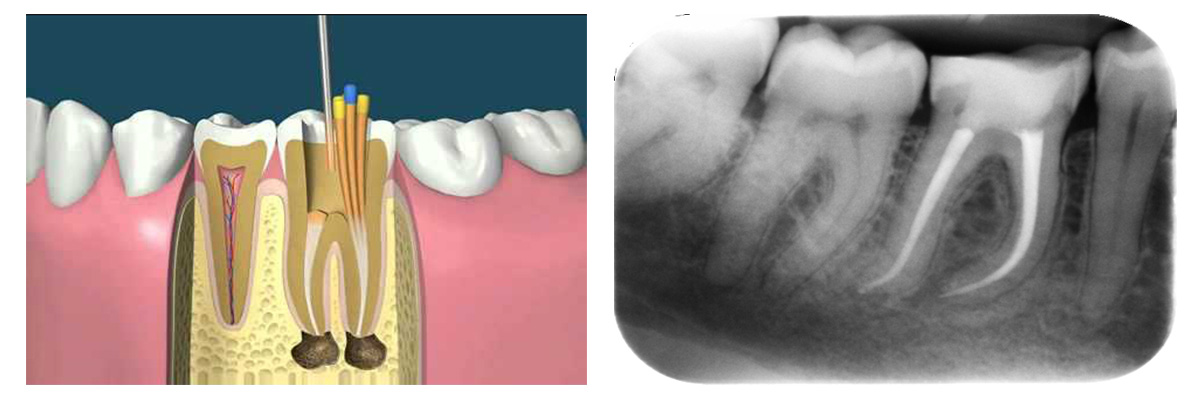

Endodontic therapy, also known as endodontic treatment or root canal therapy, is a treatment sequence for the infected pulp of a tooth which results in the elimination of infection and the protection of the decontaminated tooth from future microbial invasion. Read More